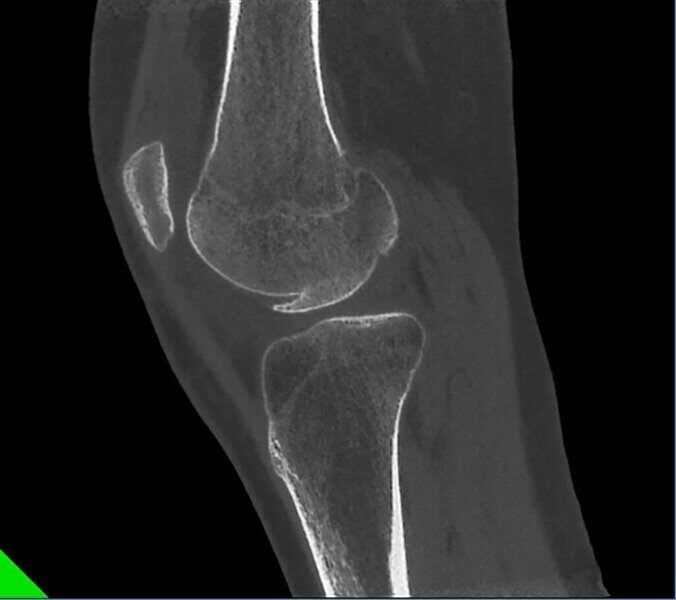

Frattura del Condilo Femorale laterale